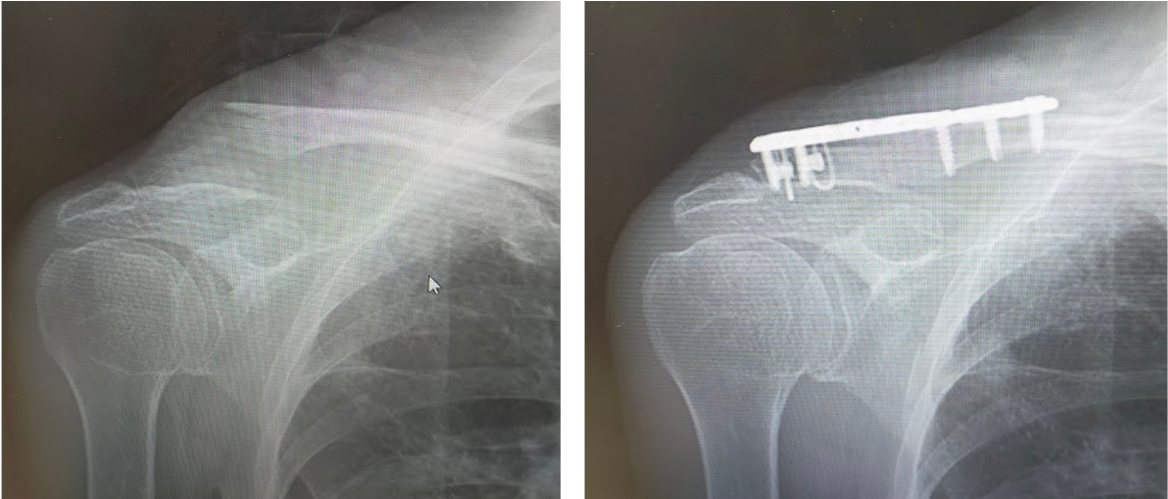

その他、上肢の骨折、足関節や下腿骨などの下肢骨折など、日常的に発生することの多いほとんどの骨折に対する治療に対応しています。

鎖骨遠位端骨折に対する骨接合術